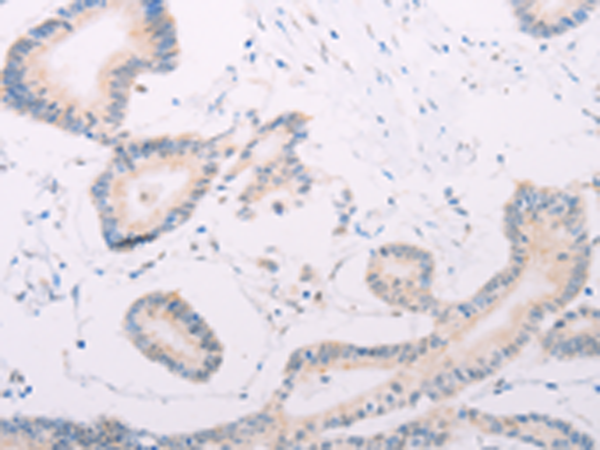

ELISA, IHC

IHC positive control:

Human colon cancer and human thyroid cancer

IHC Recommend dilution:

25-100